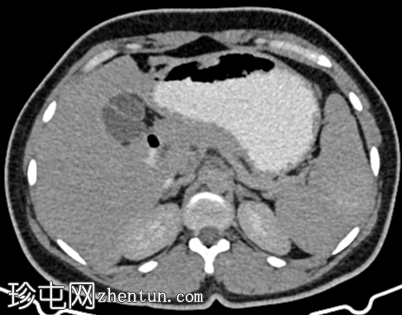

CT

轴位

平扫

脾脏内可见一圆形低密度病灶,动脉期呈周边环状强化,延迟期呈轻微向心性充盈

未见钙化、动静脉畸形或动脉瘤